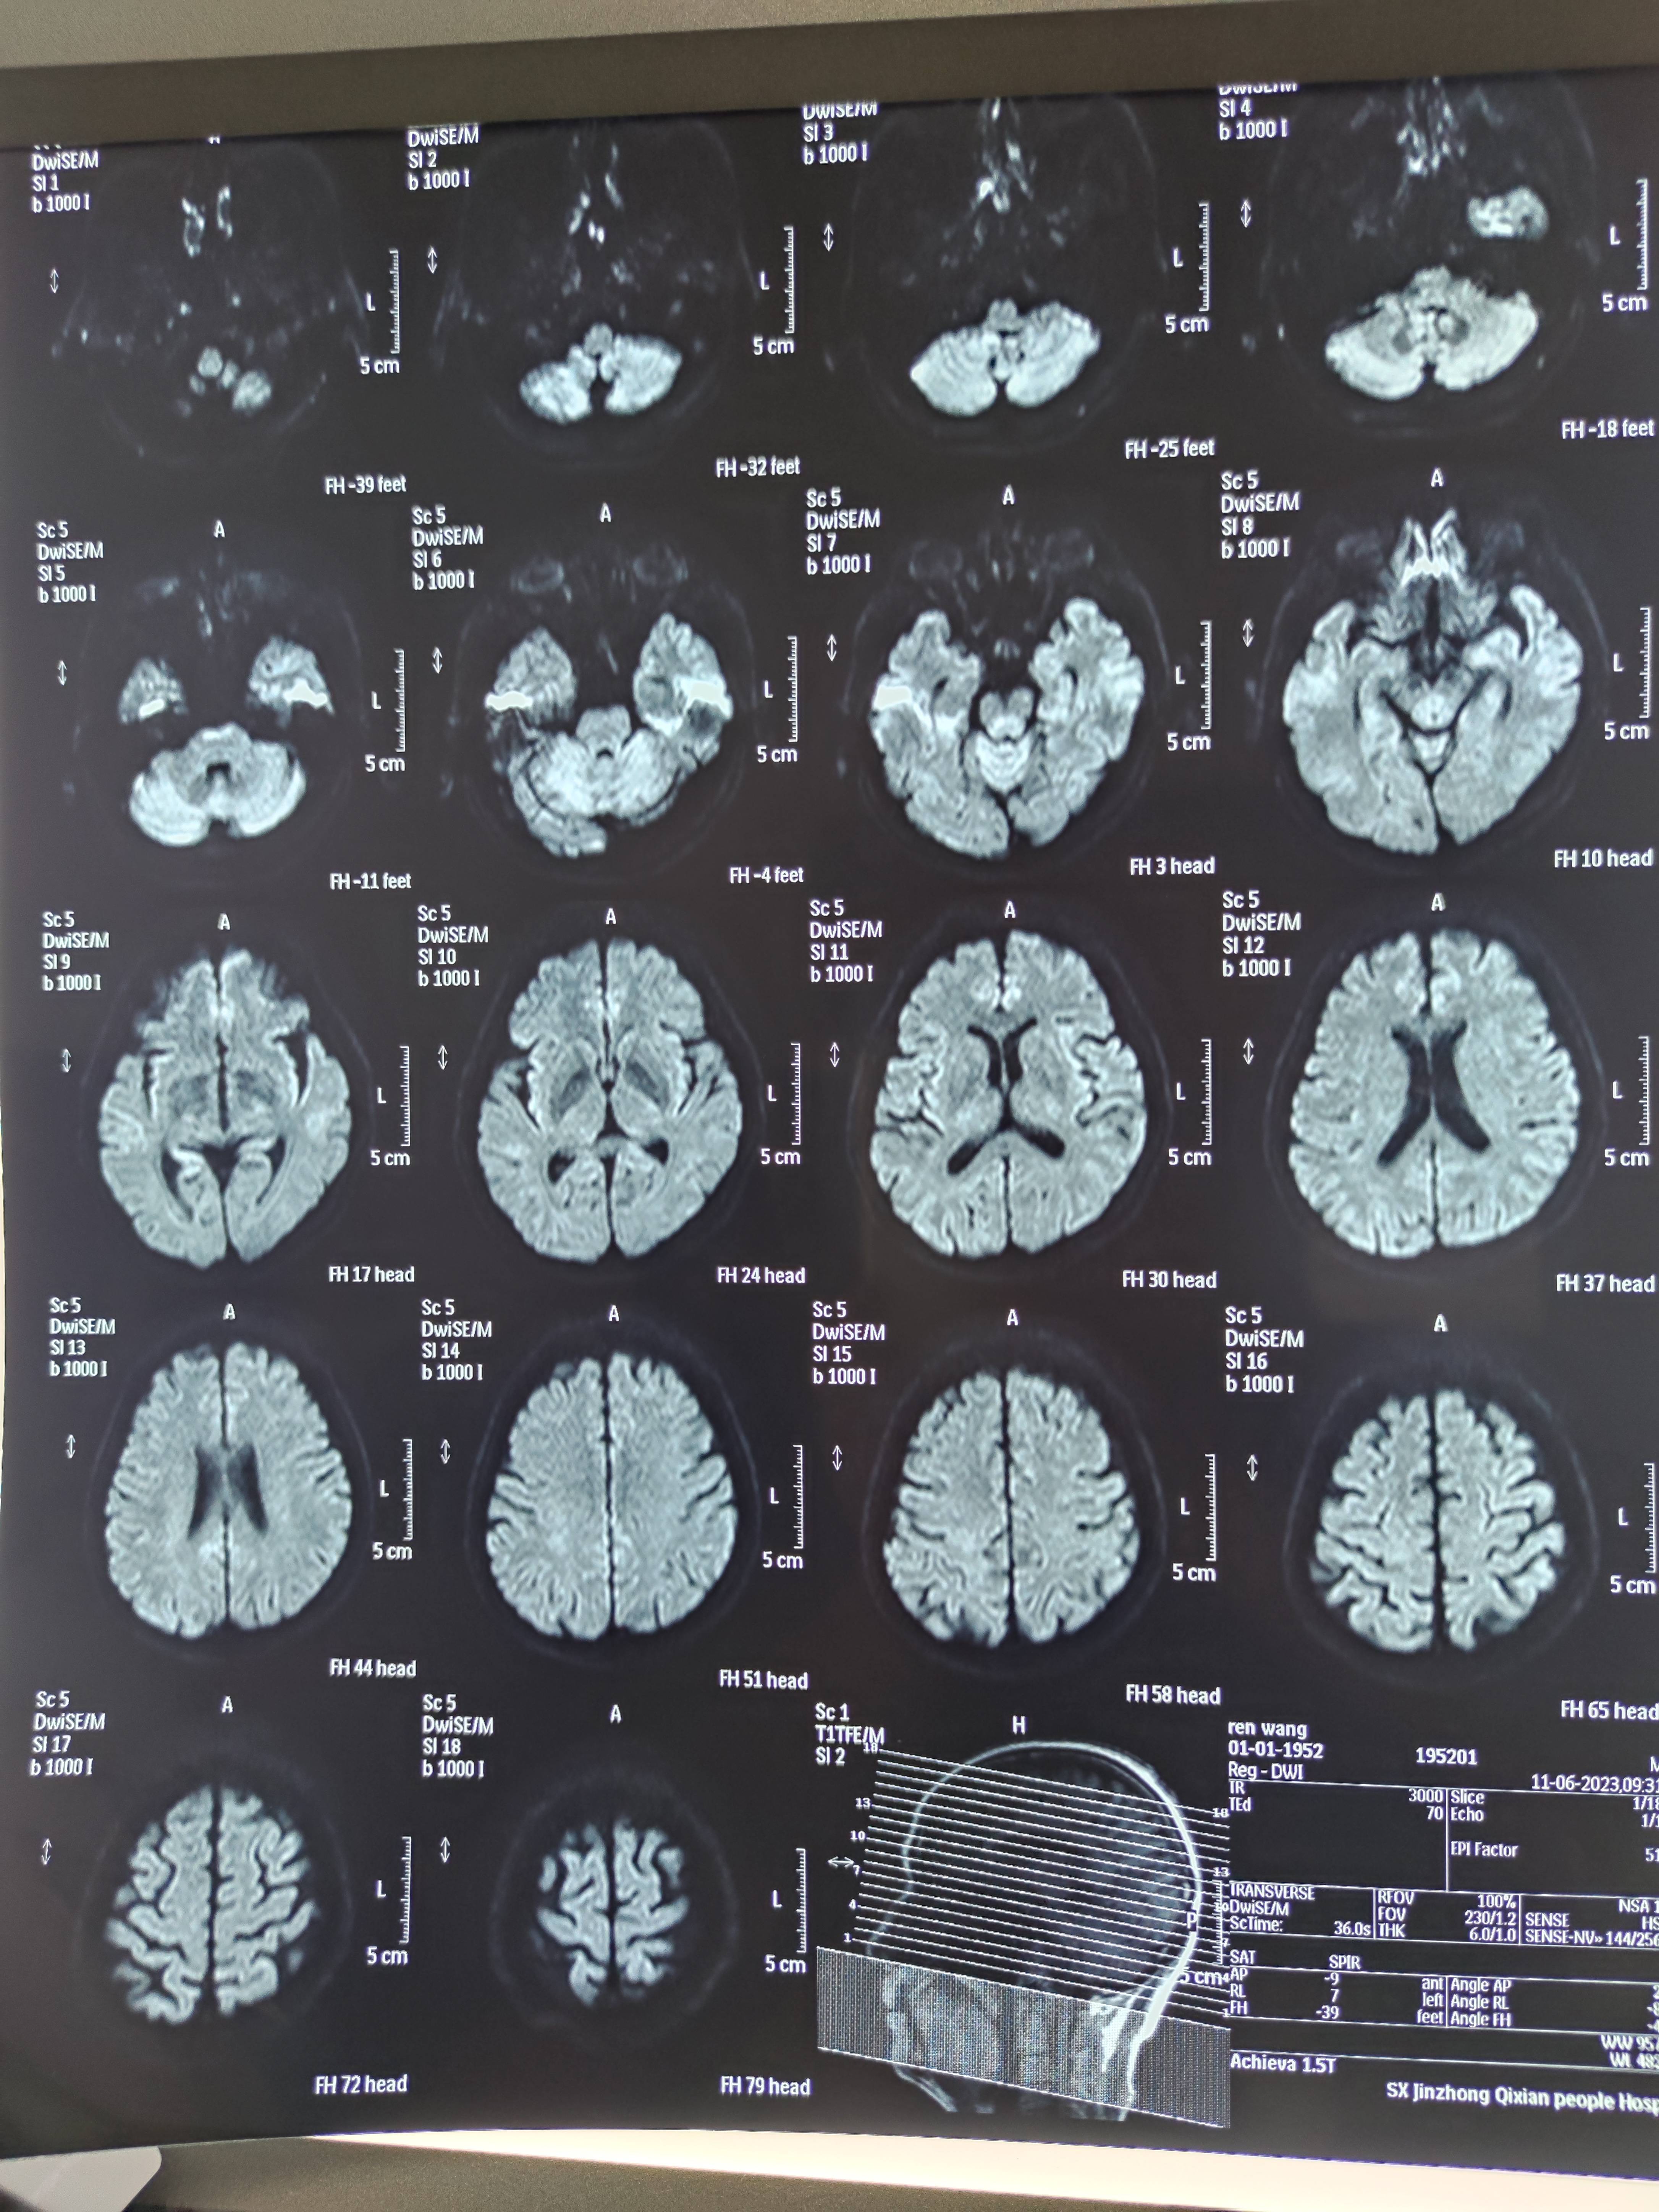

四月份癌胚抗原还是5.6,这个月到8了,持续升高。做了核磁增强,左侧桥小脑角哪有个地方不确定。肝脏核磁平扫弥散有两个点状高信号,转移也排不了,胃肠镜正常,左颈部有个变圆的淋巴结,保险点是不该加个化疗药了?咨询了陈波主任,等结果的吧!图片